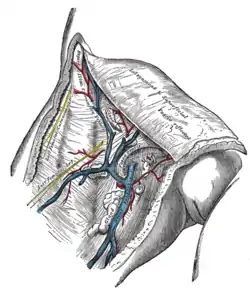

The great saphenous vein and its tributaries at the fossa ovalis.

The great saphenous vein and its tributaries at the fossa ovalis. Superficial veins of lower limb Superficial dissection. Anterior view.

Superficial veins of lower limb Superficial dissection. Anterior view.